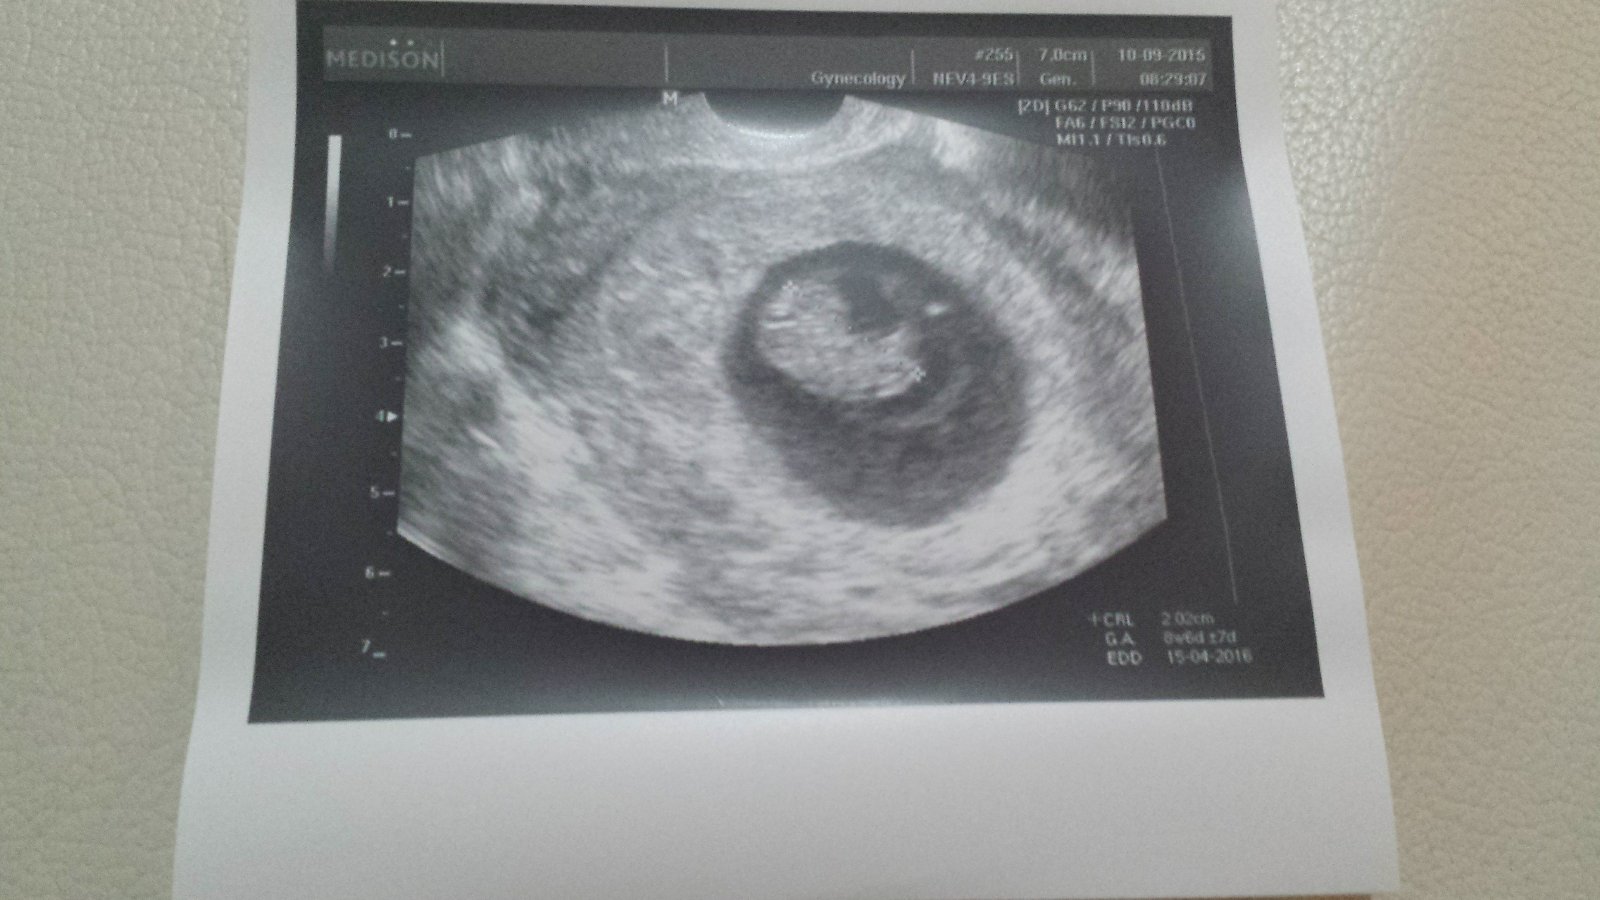

Tak kontrola za mnou...Vse v poradku,mimo odpovída 8+6tt.Zitra začínáme 3mesic🙂 Jediny co mi komplikuje život je nízký tlak:/ Dnes se mi udělalo zle při čištění zubů, vyzvracela jsem čaj a když jsem to pro dýchávala. .tak jsem omdlela a probrala se v koupelně na zemi...nikdy se mi to nestalo,strasne jsem se lekla a poradne si narazila hlavu :/ Doktorovi jsem to řekla a prej je to normální...